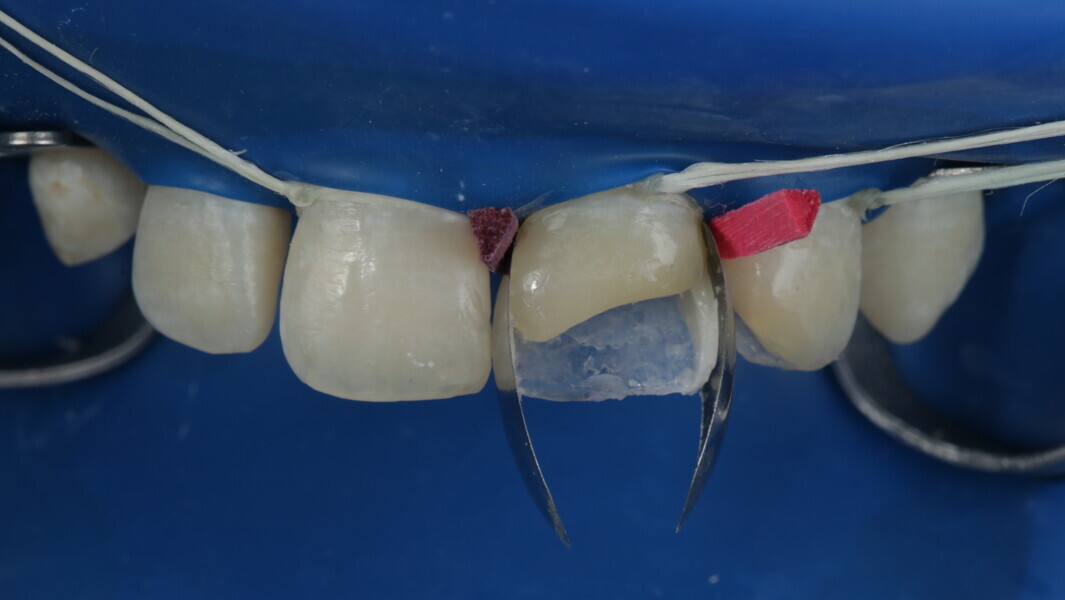

Fig 8-18: Bonding and palatal shell

Fig 19-24: Contact build-up with band and wedge